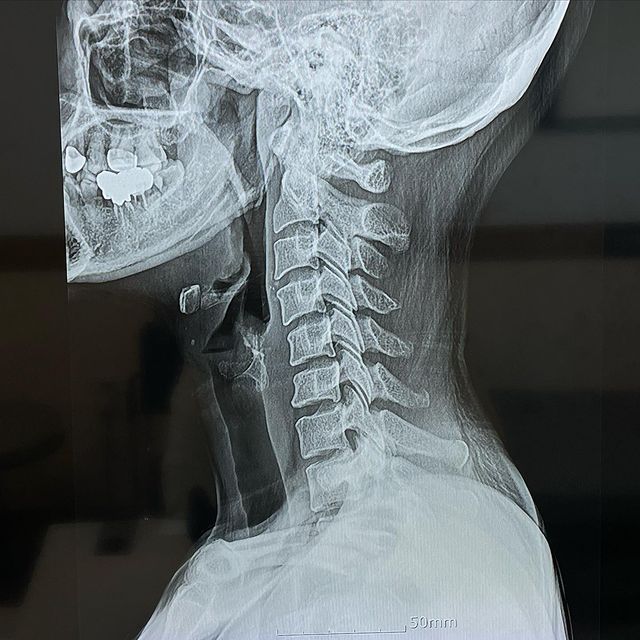

20일 아이비는 자신의 인스타그램에 "일자목을 넘어 거북목. 올 상반기 목표는 재활운동" 라는 글과 함께 사진 한 장을 게재했다.

공개된 사진은 아이비의 목뼈 엑스레이 촬영 사진이 담겼다. 이에 아이비는 "목뼈 보니 감자탕 땡기네"라는 해시태그를 남겨 너스레를 떨었다.